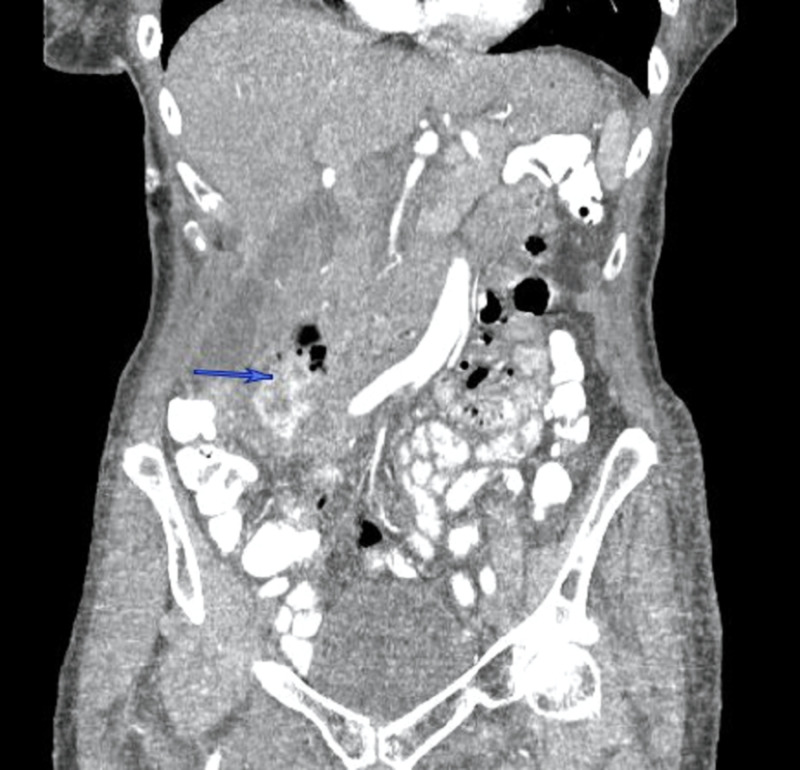

A 77-year-old healthy female presented with right-sided abdominal pain, associated with low-grade fever to 38.2 °C and mild epigastric tenderness. She was hemodynamically stable, with no significant past medical or surgical history. An outpatient CT of the abdomen (Figures 1–2) ordered by her primary care physician (PCP) revealed retroperitoneal fluid collection around the second part of the duodenum, which prompted her to be admitted to the hospital. She was found to have a low-grade fever with leukocytosis, and broad-spectrum antibiotics were immediately started. After a review of the CT images of the abdomen with the interventional radiologist, the retroperitoneal fluid collection was determined to be not amenable to percutaneous drainage. An upper gastrointestinal (GI) and small bowel study showed no evidence of perforation or leak of the stomach or duodenum. Subsequently, an upper endoscopy showed a large periampullary duodenal diverticulum with purulent drainage and normal-looking ampulla. After 72 hours of conservative management with NPO, intravenous (IV) fluid, and antibiotics, the decision was made to proceed with surgery due to persistent epigastric pain and tenderness with an interval increase in the retroperitoneal collection. She underwent excision and primary repair of the diverticulum with a jejunal serosal patch and exploration of the common bile duct (CBD) due to the proximity of the diverticulum to the ampulla. She had an uncomplicated postoperative course and was discharged home on the fourth postoperative day.